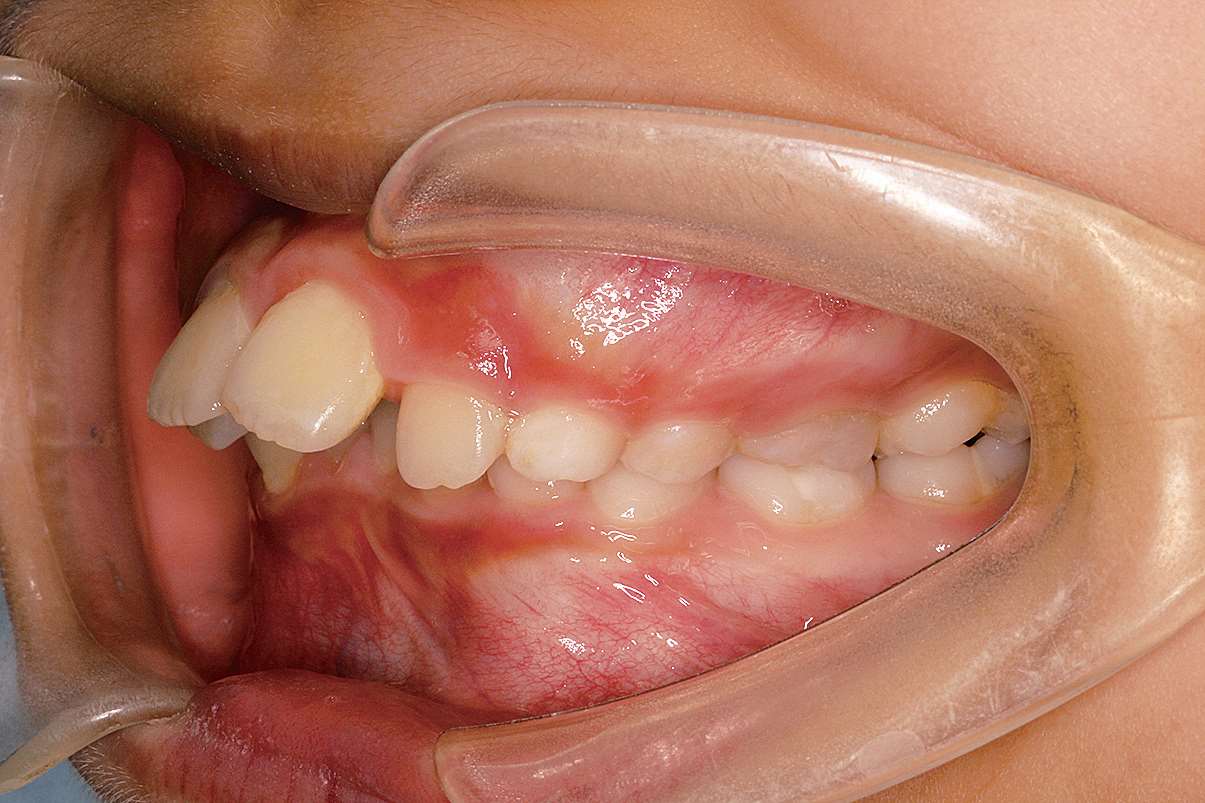

图 2-5 Ⅱ类 1 分类口内照片